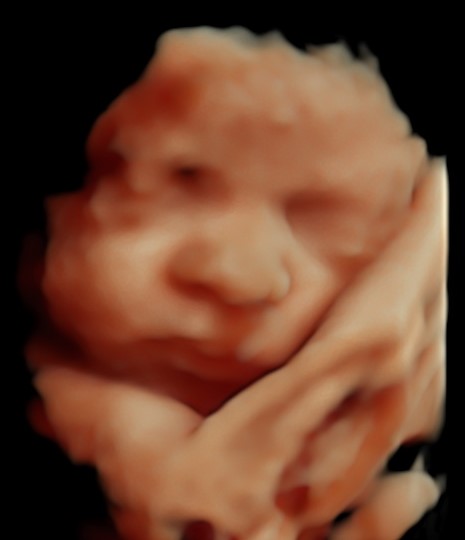

4D/5D/HD Ultrasound Gallery

Gallery